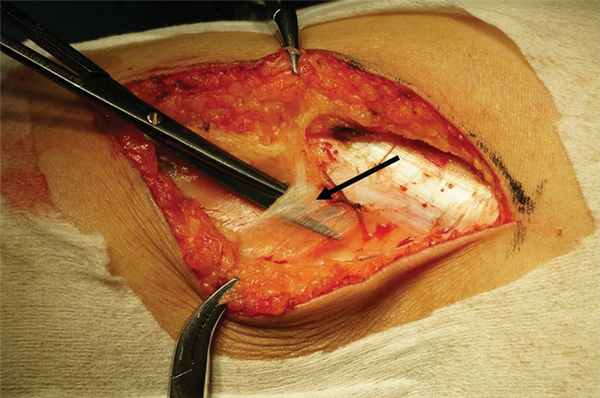

При интраоперационной ревизии основными причинами компрессии нерва являлись уплотненная поверхностная фасция, покрывающая нерв на уровне головки малоберцовой кости (рис. 1), и уплотненная фасция длинной малоберцовой мышцы (наружный и внутренний листки), которая формирует фибулярную арку на уровне перегиба нерва через малоберцовую кость и входа в малоберцовую мышцу (рис. 2).

Рис. 1. Интраоперационая фотография.

Стрелкой обозначена стенозированная фибулярная арка.

Рис. 2. Интраоперационная фотография.

Стрелкой обозначена утолщенная поверхностная фасция, перекидывающаяся с головки малоберцовой кости на латеральную головку икроножной мышцы.